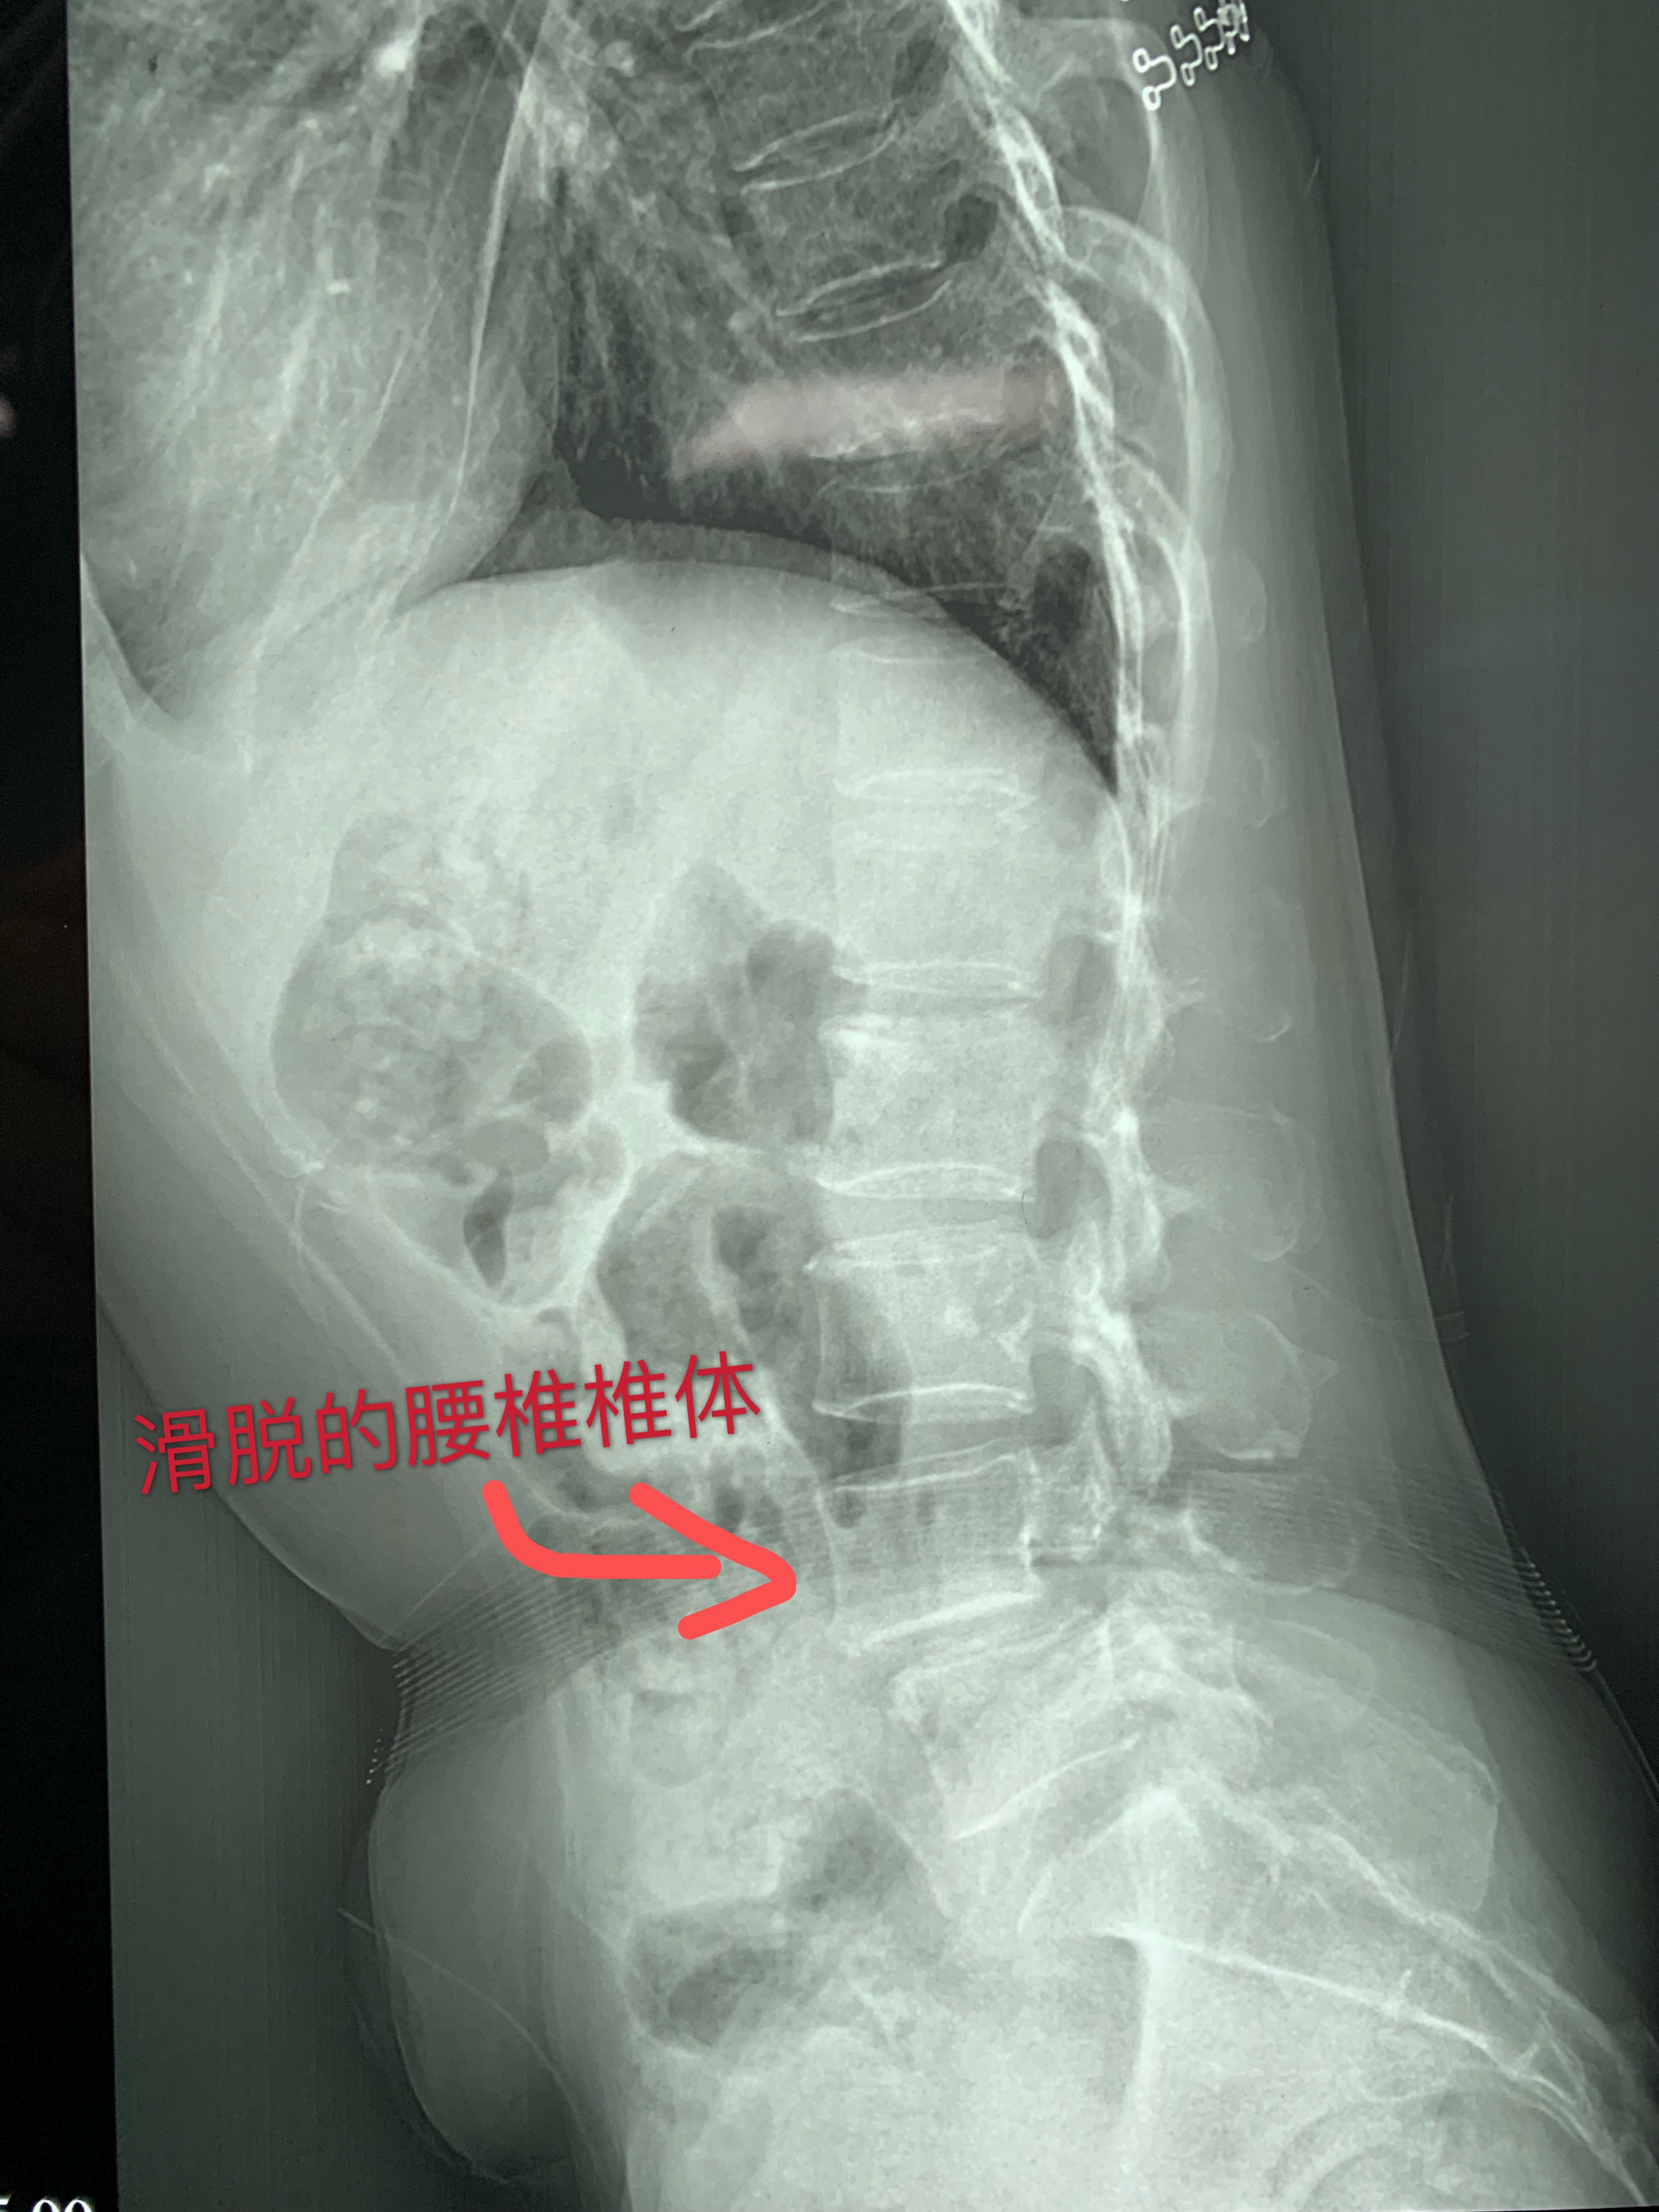

患者因反复腰腿痛伴活动受限3年,加重数月,近日无法耐受长时间行走及站立,生活质量低。曾在多家医院诊断为:1、L4/5椎间盘突出症;2、L4椎体前滑脱(Ⅰ度)。为求进一步治疗来我院就诊。入院积极完善相关术前检查,考虑传统腰椎滑脱手术时间长、创伤大、出血多。

经与顾教授详细沟通病情后,

11月7日,

戴福全主任医疗团队在顾教授技术指导下

,手术室医护人员配合下,成功的为患者实施腰椎间孔镜+OLIF手术。术后患者恢复良好,腰腿痛症状明显缓解,术后第2日患者即下地站立行走。